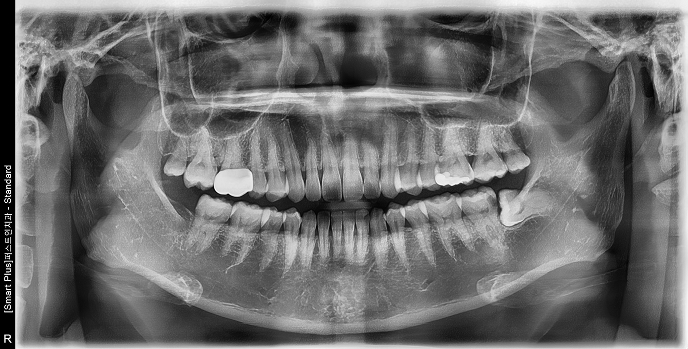

• 30대 여성 | #38 사랑니발치 | 치료기간 당일

Before 2025.03.06

After 2025.03.06